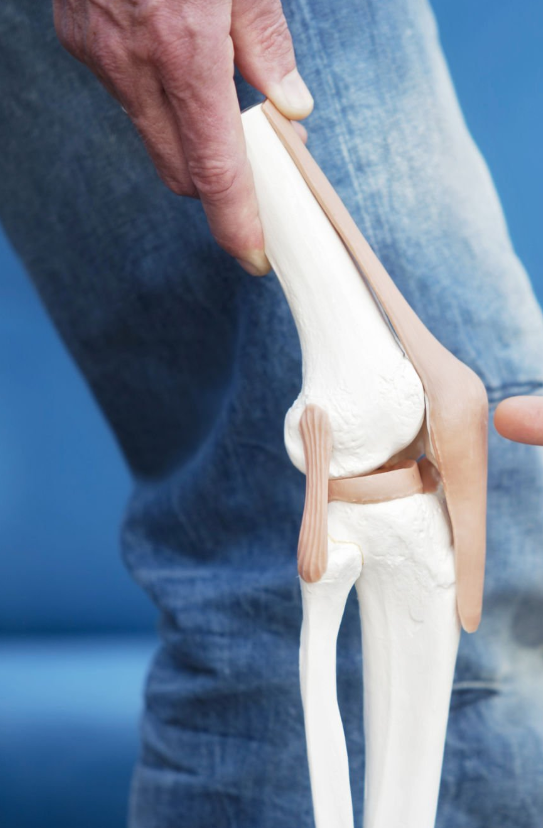

콘드로이친은 연골 내 수분을 유지하고, 이로 인해 연골이 쿠션 역할을 더 잘 할 수 있도록 돕는다고 알려져 있습니다.

따라서 관절과 뼈 사이의 마찰을 줄여주어 관절염으로 인한 통증과 뻣뻣함을 완화시킬 수 있습니다.

뿐만 아니라 연골의 깊은 부위에 영양을 공급하여 연골의 손상을 회복하고 연골세포의 신진대사를 촉진하는 역할도 합니다.